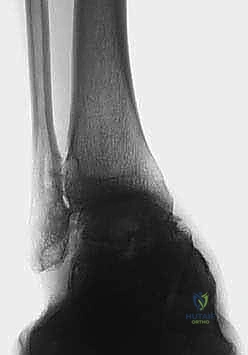

2. التصوير بالأشعة السينية بوضعية الوقوف (Weight-bearing X-rays)

هذا هو حجر الأساس في التشخيص. الأشعة العادية والمريض مستلقٍ لا تظهر الحجم الحقيقي للتشوه. يطلب الدكتور هطيف صوراً خاصة والمريض يحمل وزنه كاملاً على قدميه.

* المنظر الأمامي الخلفي (AP View): لتقييم المسافة المفصلية وتحديد زاوية سطح الساق (Tibial Anterior Surface Angle - TAS).

* منظر سالتزمان (Saltzman View): وهو منظر إشعاعي متخصص جداً لتقييم محاذاة الكعب الخلفي بالنسبة لمحور الساق، وهو أمر حاسم في التخطيط الجراحي.